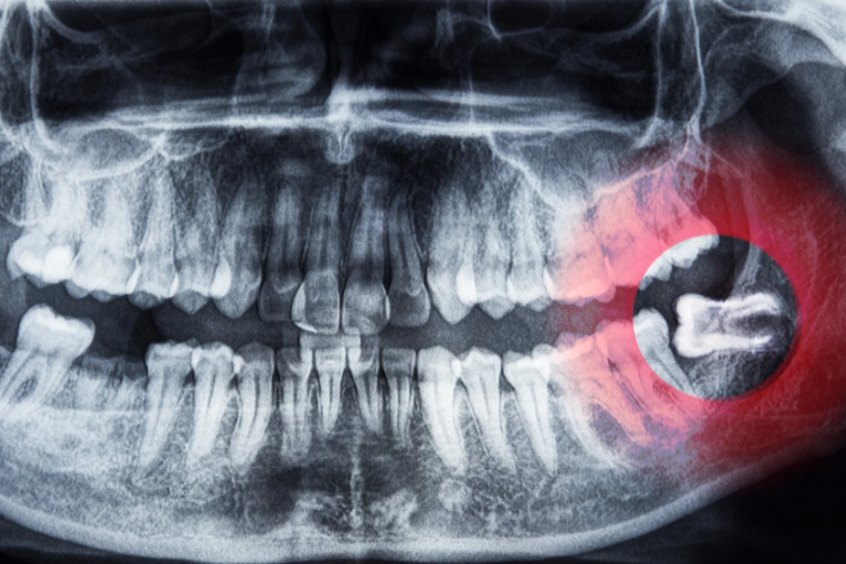

Yirmi Yaş Dişleri (üçüncü azı dişleri), ağızda en geride, alt ve üst çenenin dört köşesinde yer alan dişlerdir. Toplamda dört adet bulunurlar ve evrimsel süreçte küçülen çene yapımız nedeniyle kendilerine yer bulmakta zorlanırlar. Bir 20 lik diş, tamamen sürebilir, yarı gömülü kalabilir veya çene kemiği içinde gömülü diş olarak kalabilir. Gömülü kalma durumu, en sık komplikasyonların kaynağıdır.

- Kist veya Tümör Oluşumu: Gömülü dişin etrafında kist veya tümör gelişme riski veya oluşumu (foliküler kist).

- Kist ve Tümör Riski: Gömülü dişin folikülü zamanla büyüyerek çene kemiğini tahrip eden kistlere dönüşebilir.

Özellikle alt çenedeki gömülü 20 lik dişlerin çekimi, alt çene sinirine (Nervus Alveolaris İnferior – IAN) olan yakınlıkları nedeniyle risk taşıyabilir. Bu sinir, dudak ve çene ucu bölgesinin hissini sağlar.

CBCT (Konik Işınlı Bilgisayarlı Tomografi), 2025 yılında güvenli gömülü diş çekimi için kritik öneme sahiptir. CBCT planlama, dişin ve köklerin sinir kanalına olan mesafesini, açısını ve üç boyutlu ilişkisini milimetrik olarak haritalar. Bu, cerrahın operasyon öncesinde en güvenli cerrahi yolu belirlemesini ve sinir hasarı riskini minimuma indirmesini sağlar.